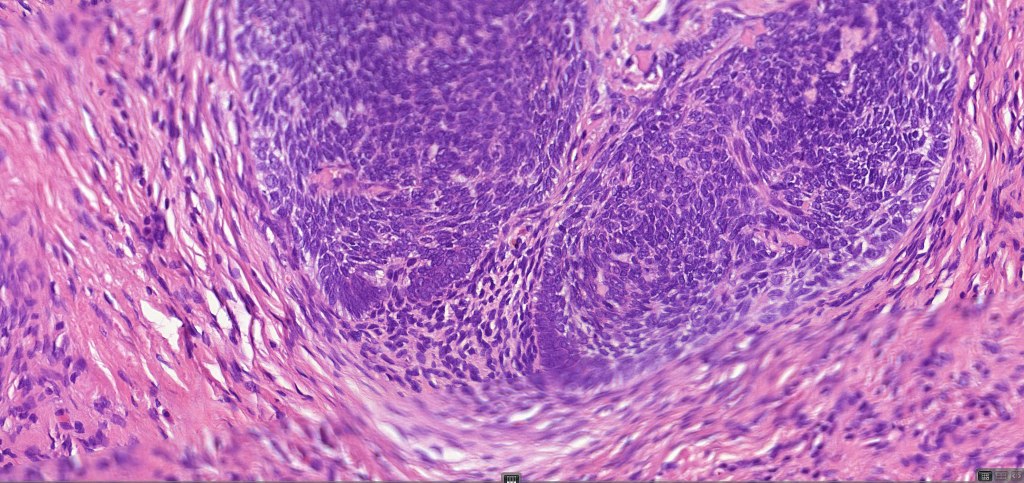

•Variably sized but generally large, basophilic tumor nodules composed of small uniform basaloid cells with minimal cytoplasm

•Peripheral palisading but no retraction artifact or stromal mucin deposition

•A rich fibromyxoid mesenchymal stroma with variable papillary mesenchymal bodies (sometimes these are absent)